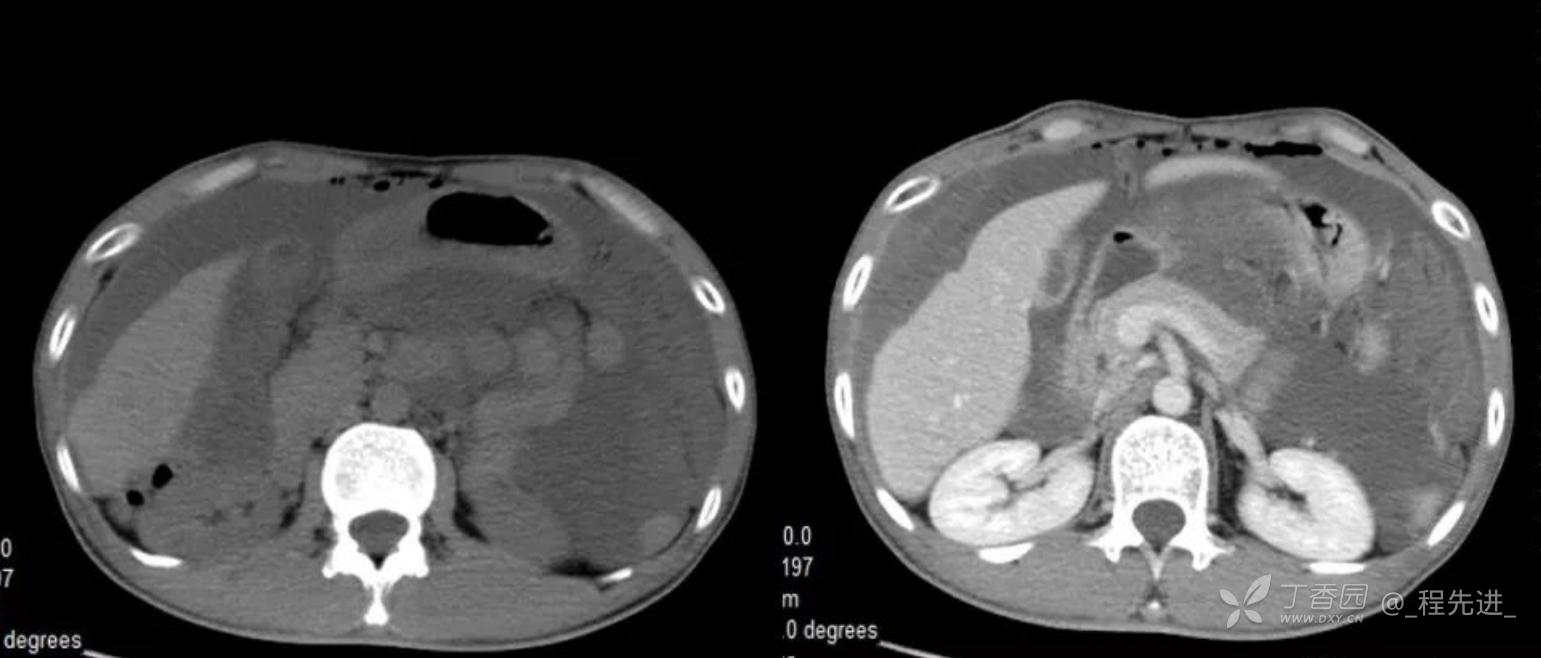

患者性别:男

患者年龄:46岁

主诉:腹胀10余天

现病史:患者10余天前无诱因腹胀,进食后加重,便后缓解,余无特殊

腹膜假黏液瘤 (5)